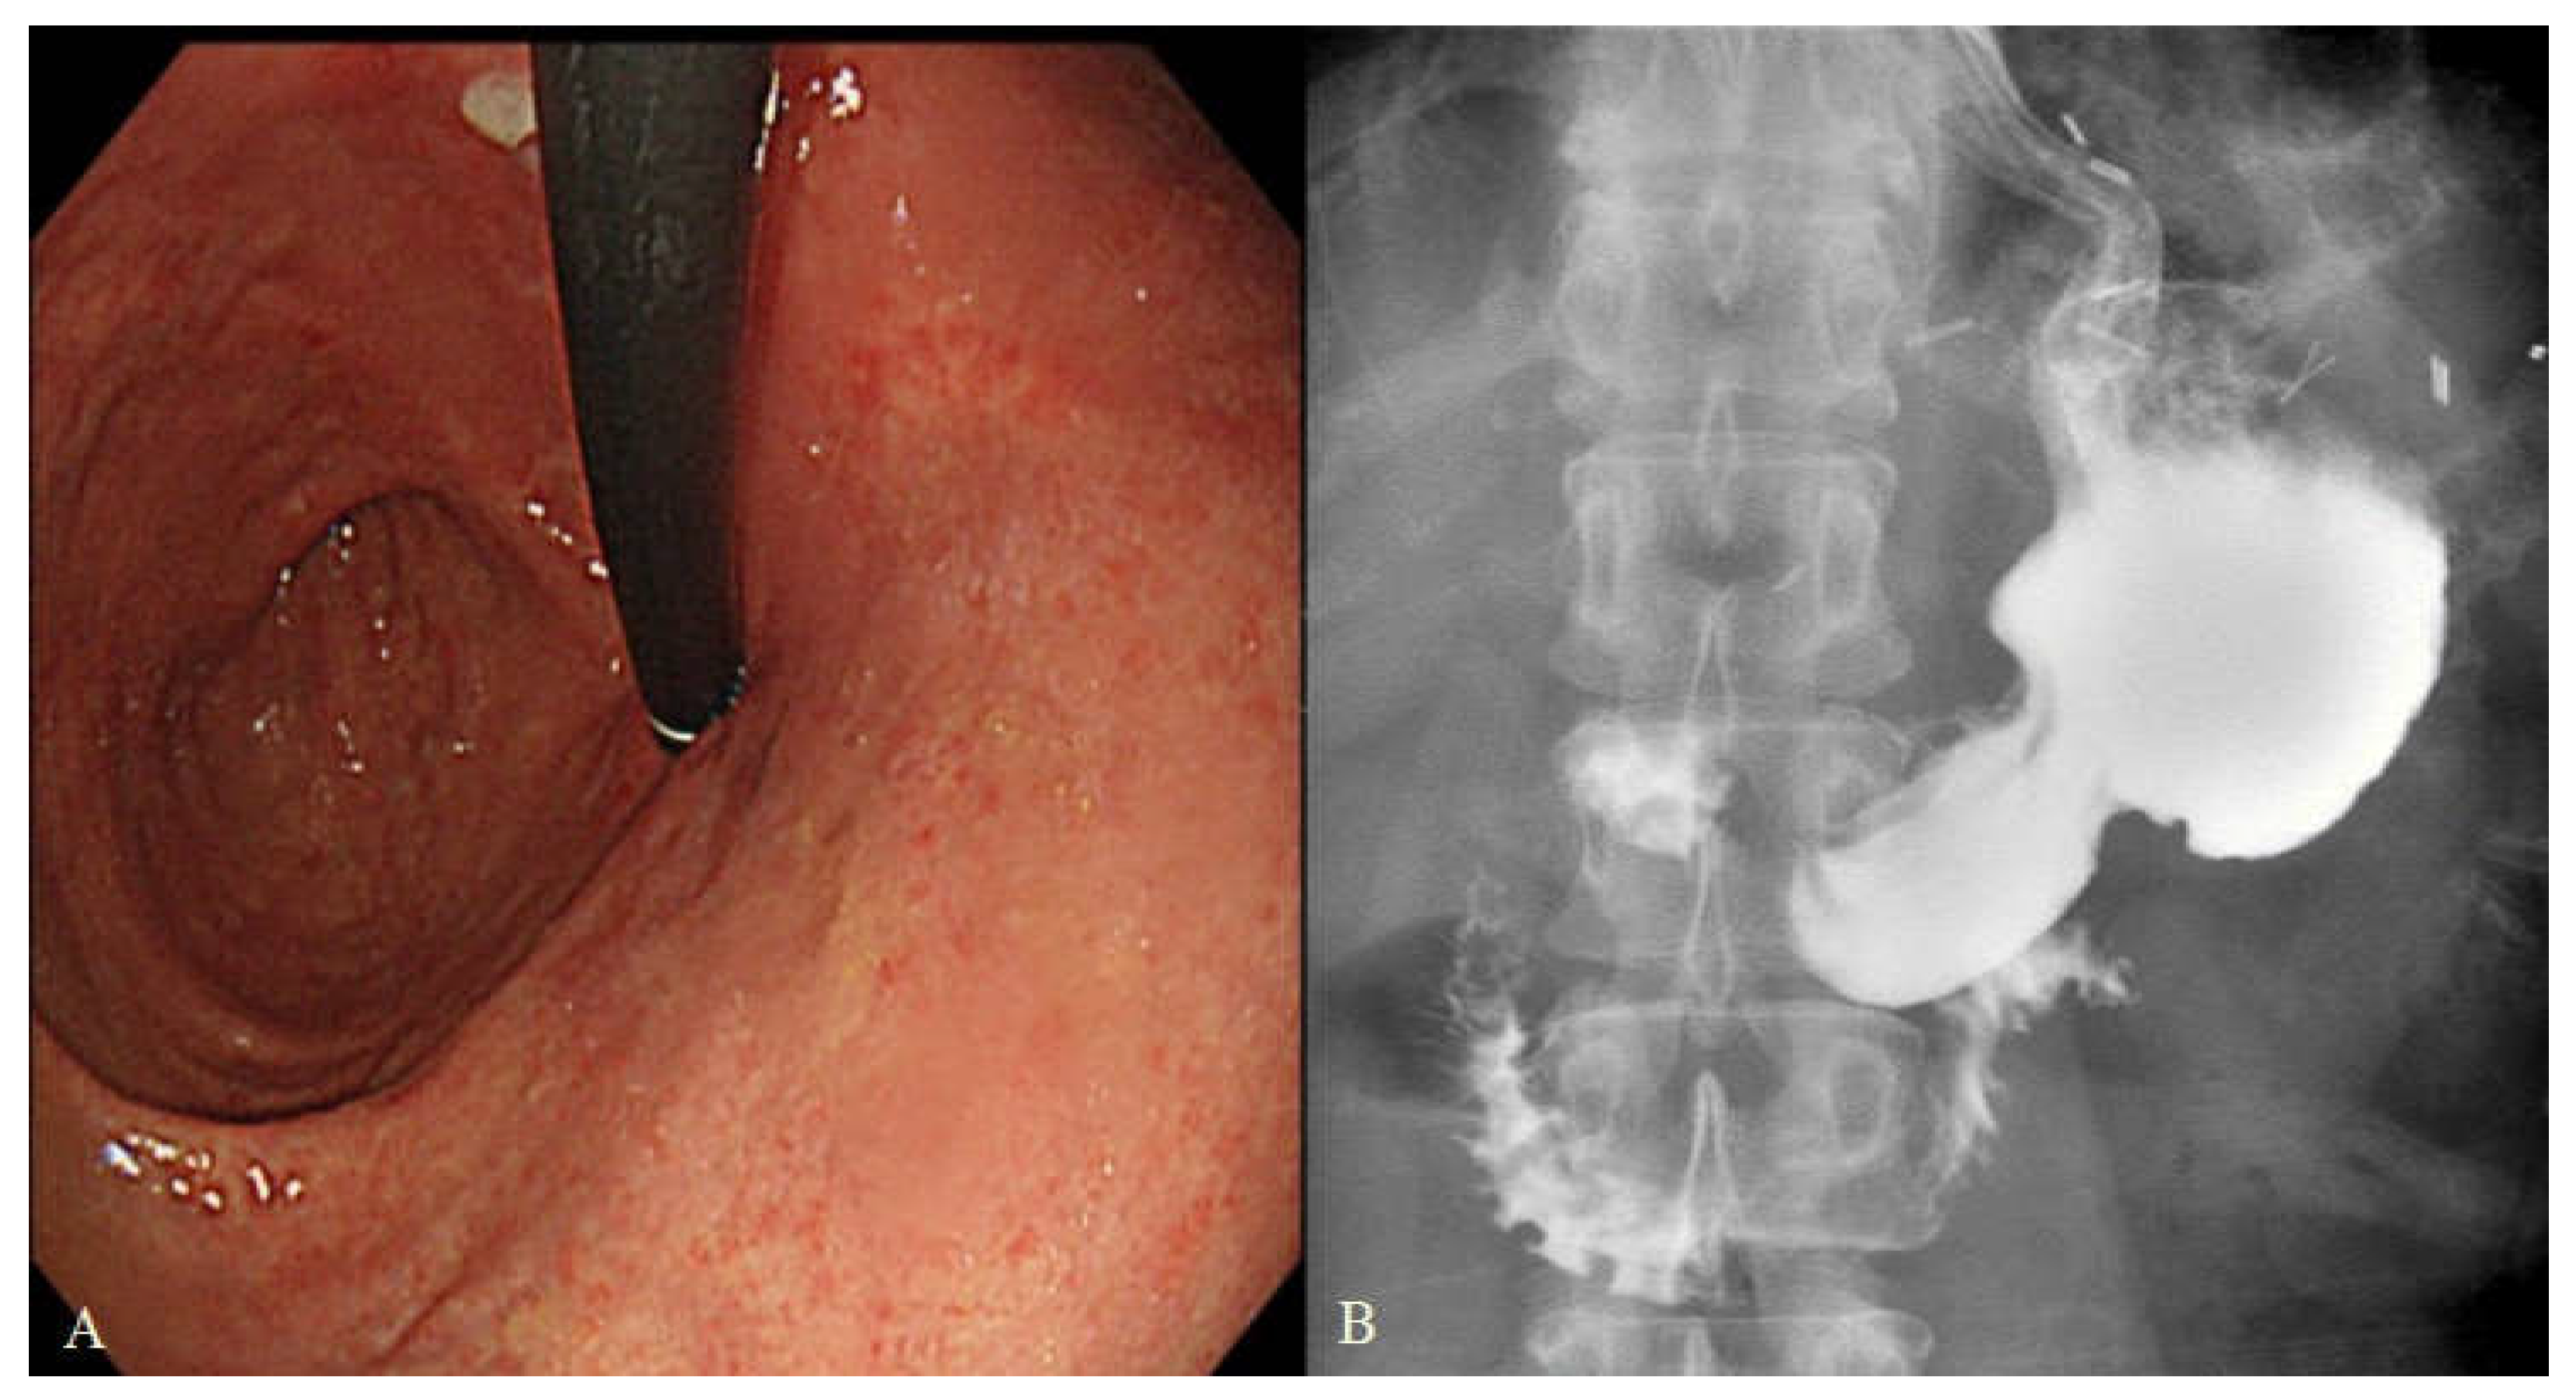

| Reflux esophagitis in EGD | |

| No | 33 (97.1%) |

| LA-A | 0 (0%) |

| LA-B | 1 (2.9%) |

| LA-C | 0 (0%) |

| Bile reflux in EGD | |

| Grade 0 | 28 (82.4%) |

| Grade 1 | 6 (17.6%) |

| Residual food in EGD | |

| Grade 0 | 18 (52.9%) |

| Grade 1 | 3 (8.8%) |

| Grade 2 | 3 (8.8%) |

| Grade 3 | 10 (29.4%) |

| Reflux symptoms | |

| No symptom | 28 (82.4%) |

| Mild symptom | 5 (14.7%) |

| Moderate symptom | 1 (2.9%) |

| Severe symptom | 0 (0%) |